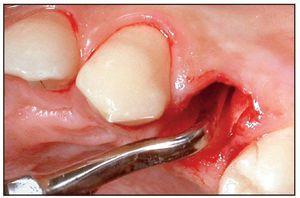

La extracción se efectuó usando las puntas del equipo de extracción (figura 1). La punta en forma de flecha se introdujo en el surco a una profundidad de 4-5 mm sin separar primero la encía del diente, alrededor de toda la circunferencia de éste. No se evidenció hemorragia mientras se progresaba en dirección apical (figuras 3a y 3b). Acto seguido, se usaron sindesmotomos rectos o angulados para cortar en profundidad las fibras del LPD (hasta 10 mm o más). Tras la sección de las fibras del ligamento, el diente se movilizó con un sindesmotomo de Claude Bernard (figura 3c) y se extrajo del alveolo con unas pinzas (figura 3d). En el caso de dientes anquilosados, se usaron sindesmotomos de vibración para desprender la raíz del hueso fijado circundante.

Figura 3 Procedimiento de extracción con las puntas vibratorias.

Figuras 3a y 3b La punta en forma de flecha se introdujo en el ligamento periodontal en el lado distal (derecha) y el lado mesial (izquierda) del diente afectado.